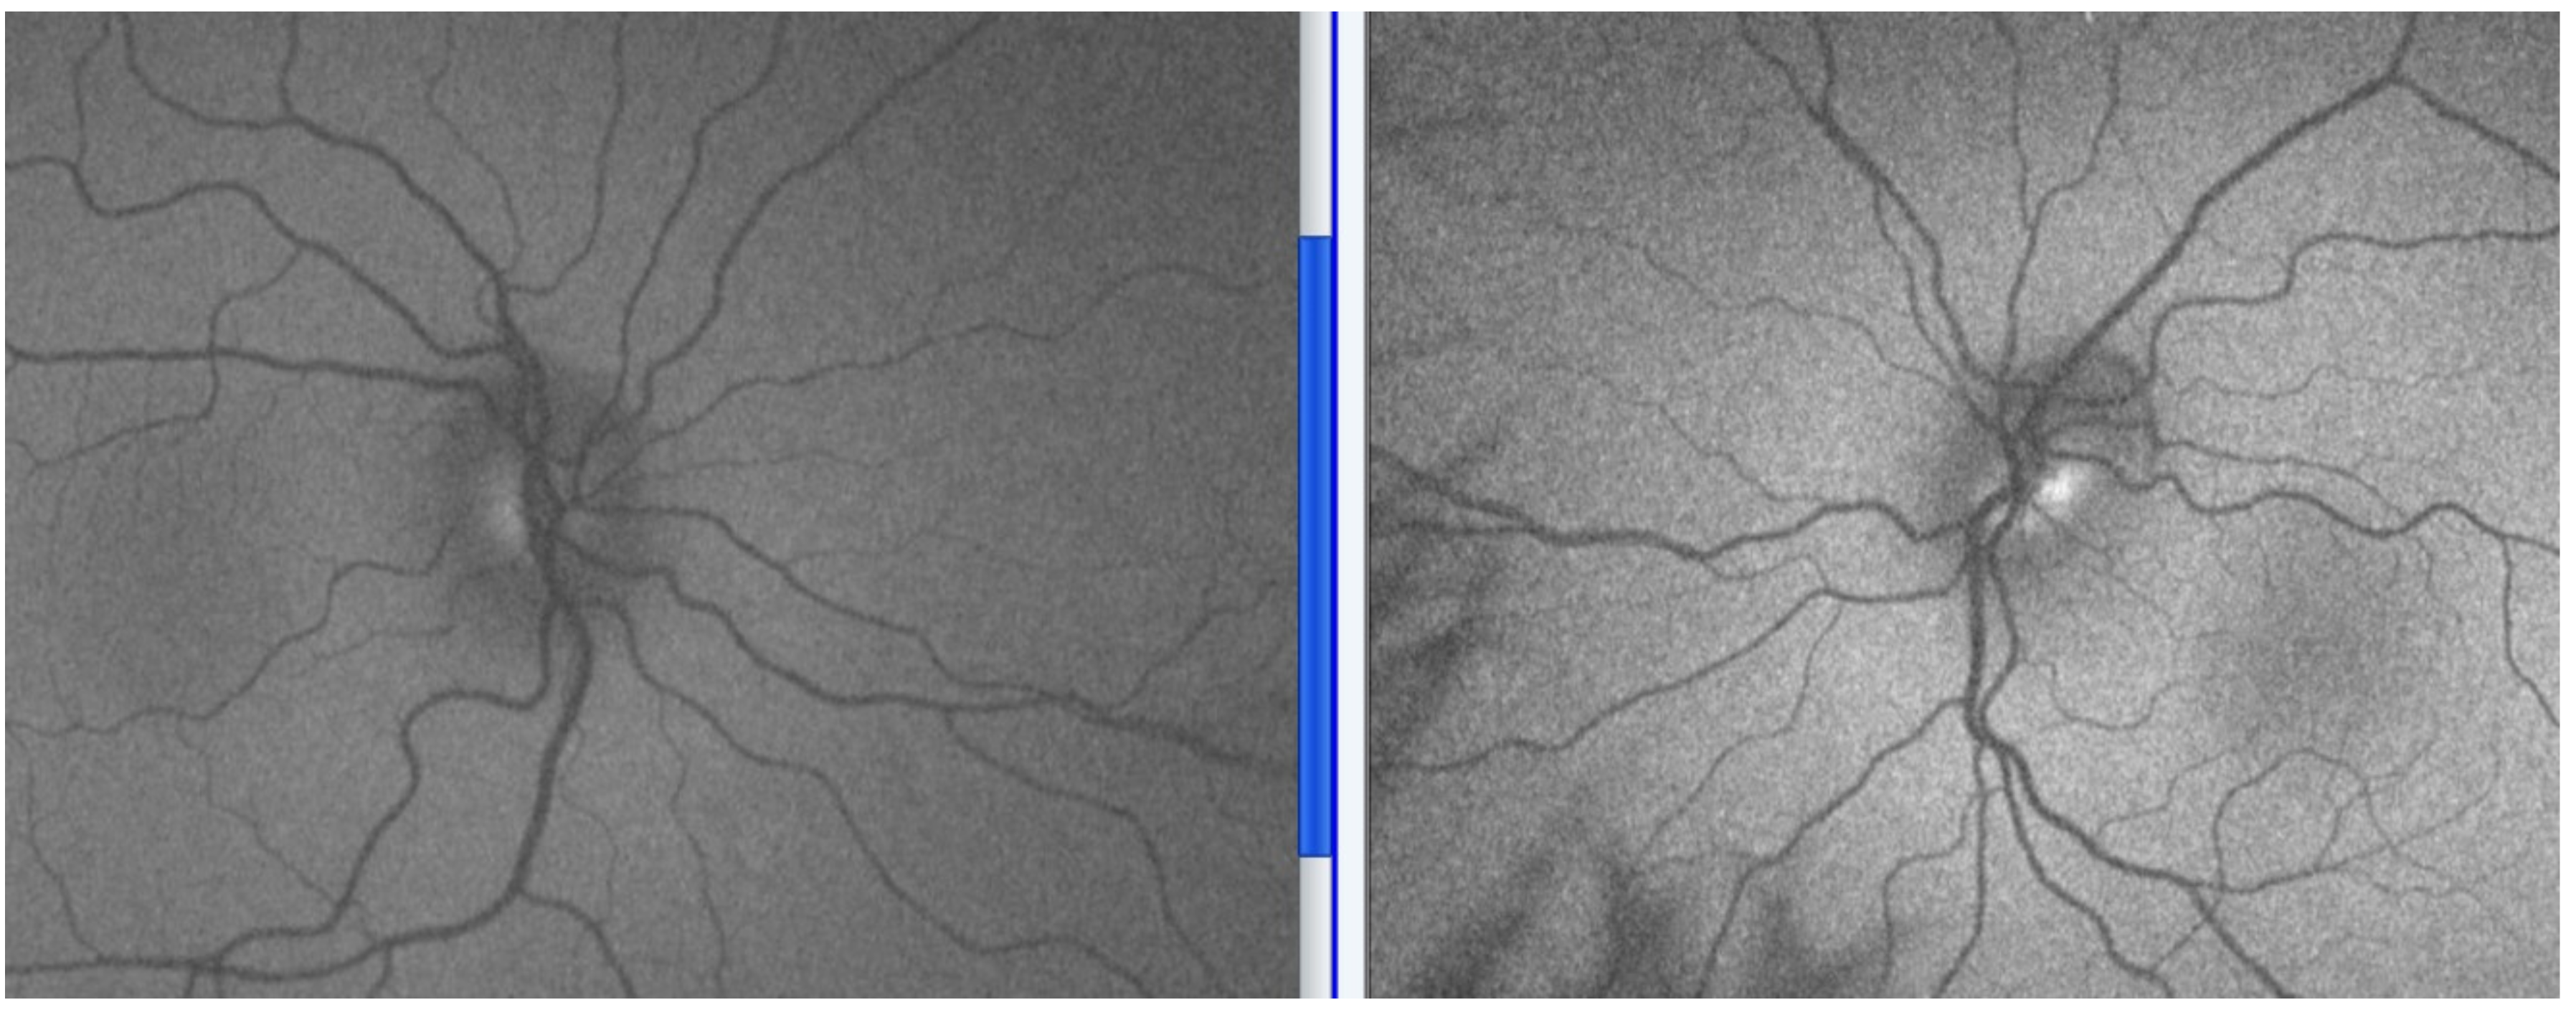

5.2. Signs

Examination and Investigations